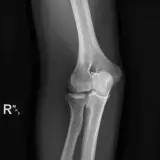

Over 2,100 interactive radiology cases, curated by radiologists for your level of training. Scroll, window, and view cases full screen โ€” just like on PACS. Click linked findings in each writeup to jump straight to them on the image. Cases include sample reports, a focused discussion section, original illustrations, and videos.

Casi completamente interattivi con gli strumenti che ti aspetti su un PACS: scroll, windowing, zoom, pan, misurazioni, ROI e modalitร  a schermo intero.

Annotazioni dettagliate evidenziano i reperti chiave direttamente sui casi. Clicca sui reperti collegati nella descrizione del caso per saltare alla loro esatta posizione sullo scan.